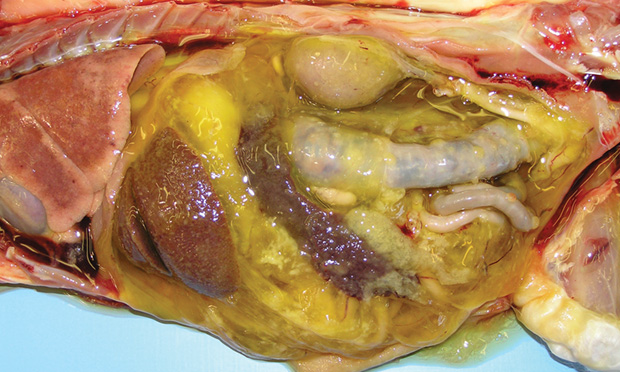

Wet feline infectious peritonitis top

Wet feline infectious peritonitis top, Feline Infectious Peritonitis 2014 top

Wet feline infectious peritonitis top

Feline Infectious Peritonitis 2014